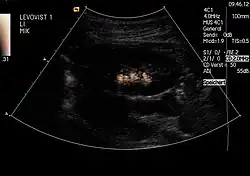

Kontrastmittel in der Harnblase mit Reflux in den linken Harnleiter

Kontrastmittel im Nierenbecken der linken Niere

Um einen Rückfluss (Reflux) von Urin aus der Blase in die Niere auszuschließen: Diese Untersuchung, genannt Miktionsurosonografie (MUS), kann die bisher durchgeführte Röntgenuntersuchung mit Kontrastmittel (Miktionscystourogramm, MCU) ersetzen. Auf diese Weise ist also eine Refluxprüfung ohne Strahlenbelastung möglich. Da die empfindlichen Gonaden bei der Röntgenuntersuchung regelmäßig mit im Nutzstrahlenbündel liegen, ist dies ein großer Vorteil.